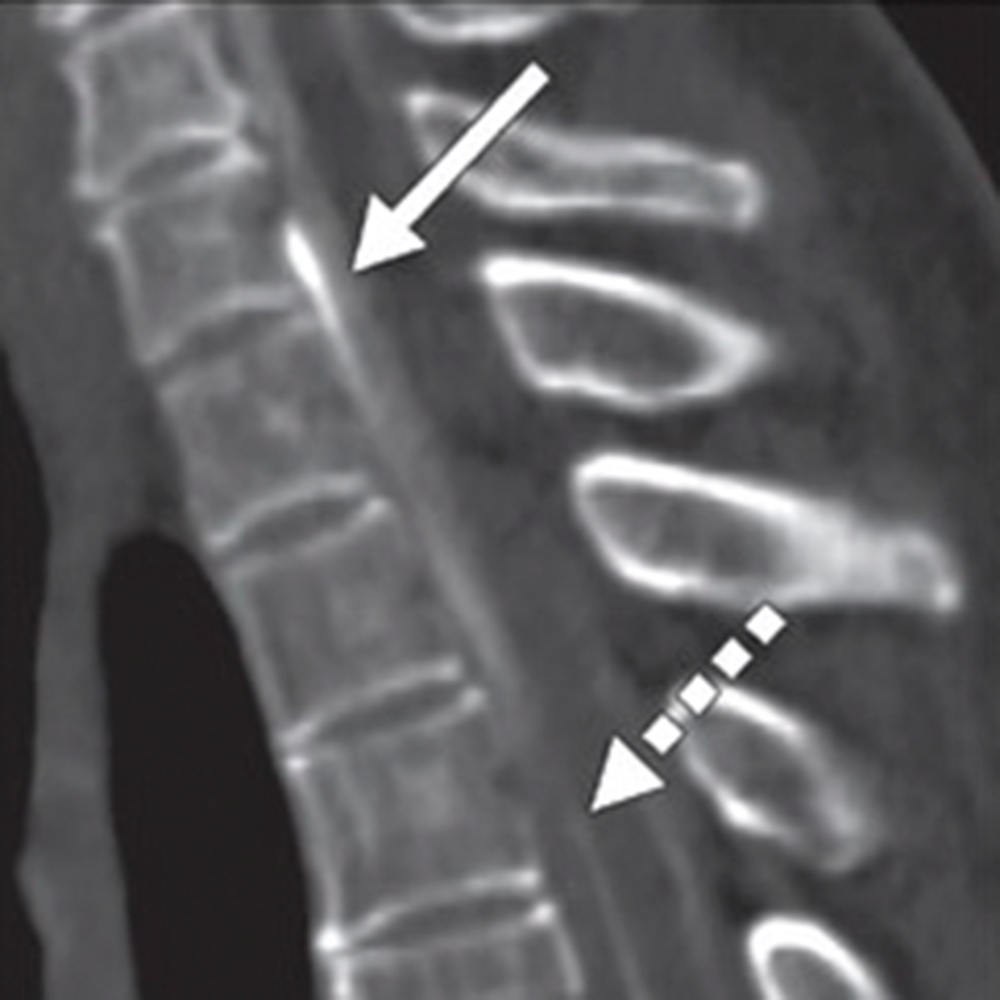

As TAVR becomes more common, the rad’s role is expanding from procedural planning to risk stratification.